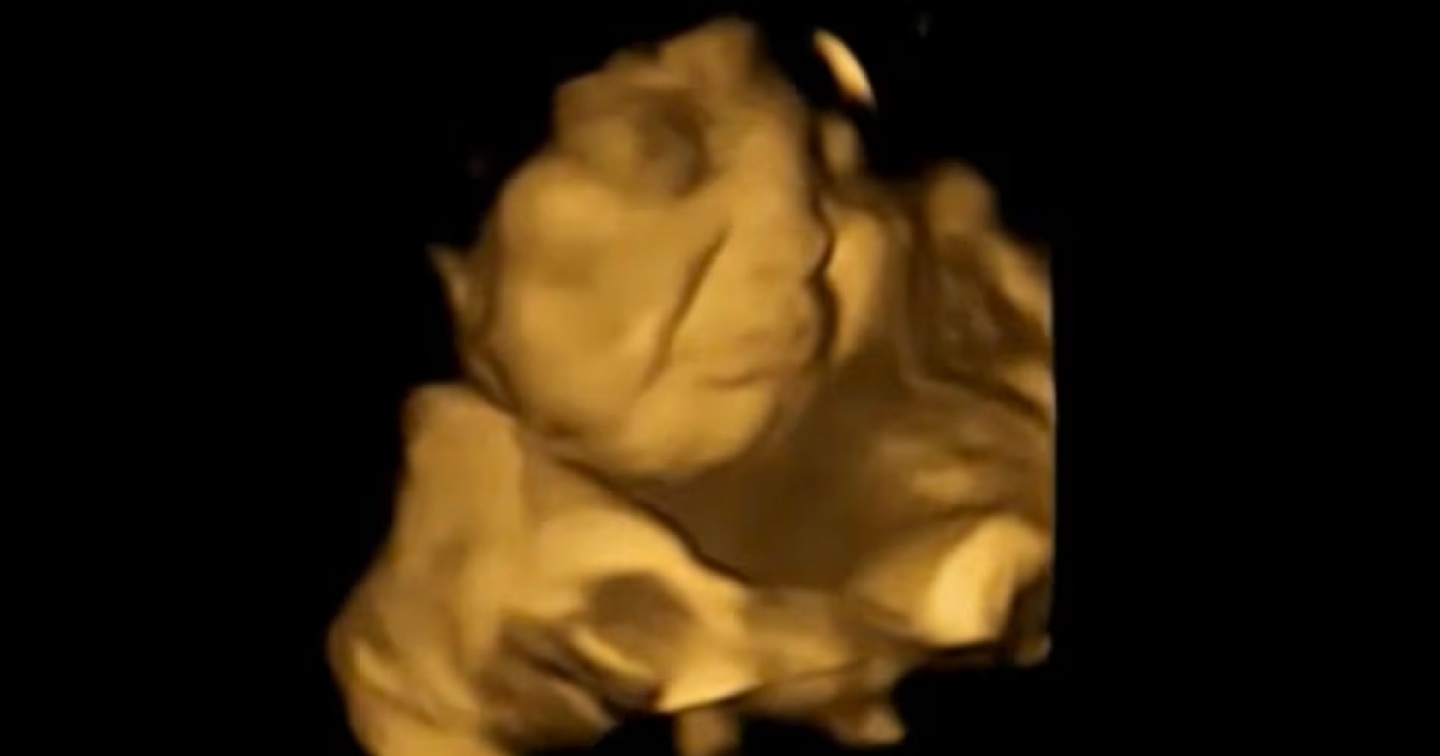

I feti che avevano "assaggiato" la carota hanno mostrato tutti un'espressione simile a una risata molto ben riconoscibile (vedi foto in apertura); quelli a cui è toccato il cavolo hanno fatto una smorfia più simile a un pianto, come si vede nell'immagine qui sotto. Le madri non avevano mangiato o bevuto nient'altro che potesse interferire, prima dell'ecografia, e i feti del gruppo di controllo, non esposti ad alcun sapore, non hanno mostrato alcuna espressione in comune particolare.